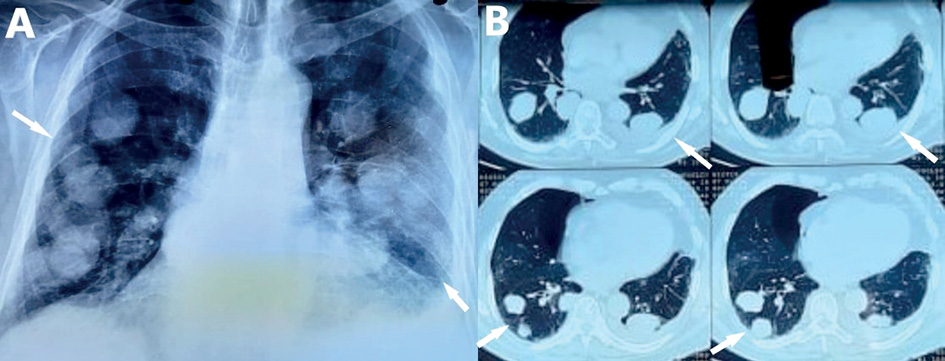

Complete blood count revealed normochromic normocytic anemia and the coagulation tests were normal. The other blood biochemistry parameters were normal, with the exception of an elevated serum lactate dehydrogenase (LDH) 501 U/L (normal <225 U/L). Chest X-ray revealed multiple pulmonary nodules and left pleural effusion (Figure 1A).

The patient underwent computed tomography (CT) of the chest and abdominal CT. Chest CT showed several nodules of various size in all lung fields, ground glass opacities and a small left pleural effusion (Figure 1B), while from abdomen CT no suspicious abnormality of solid organs was noted.